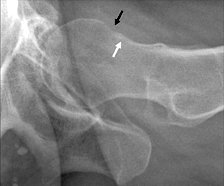

Lateral hip pincer-type impingement with linear erosion.

Pincer-type impingement demonstrates overcoverage of the acetabulum in relationship to the femoral head and a linear indentation at the head-neck junction of the femur. There are many ways of measuring the depth of the acetabulum. A software program has even been developed to determine the depth of the acetabulum.